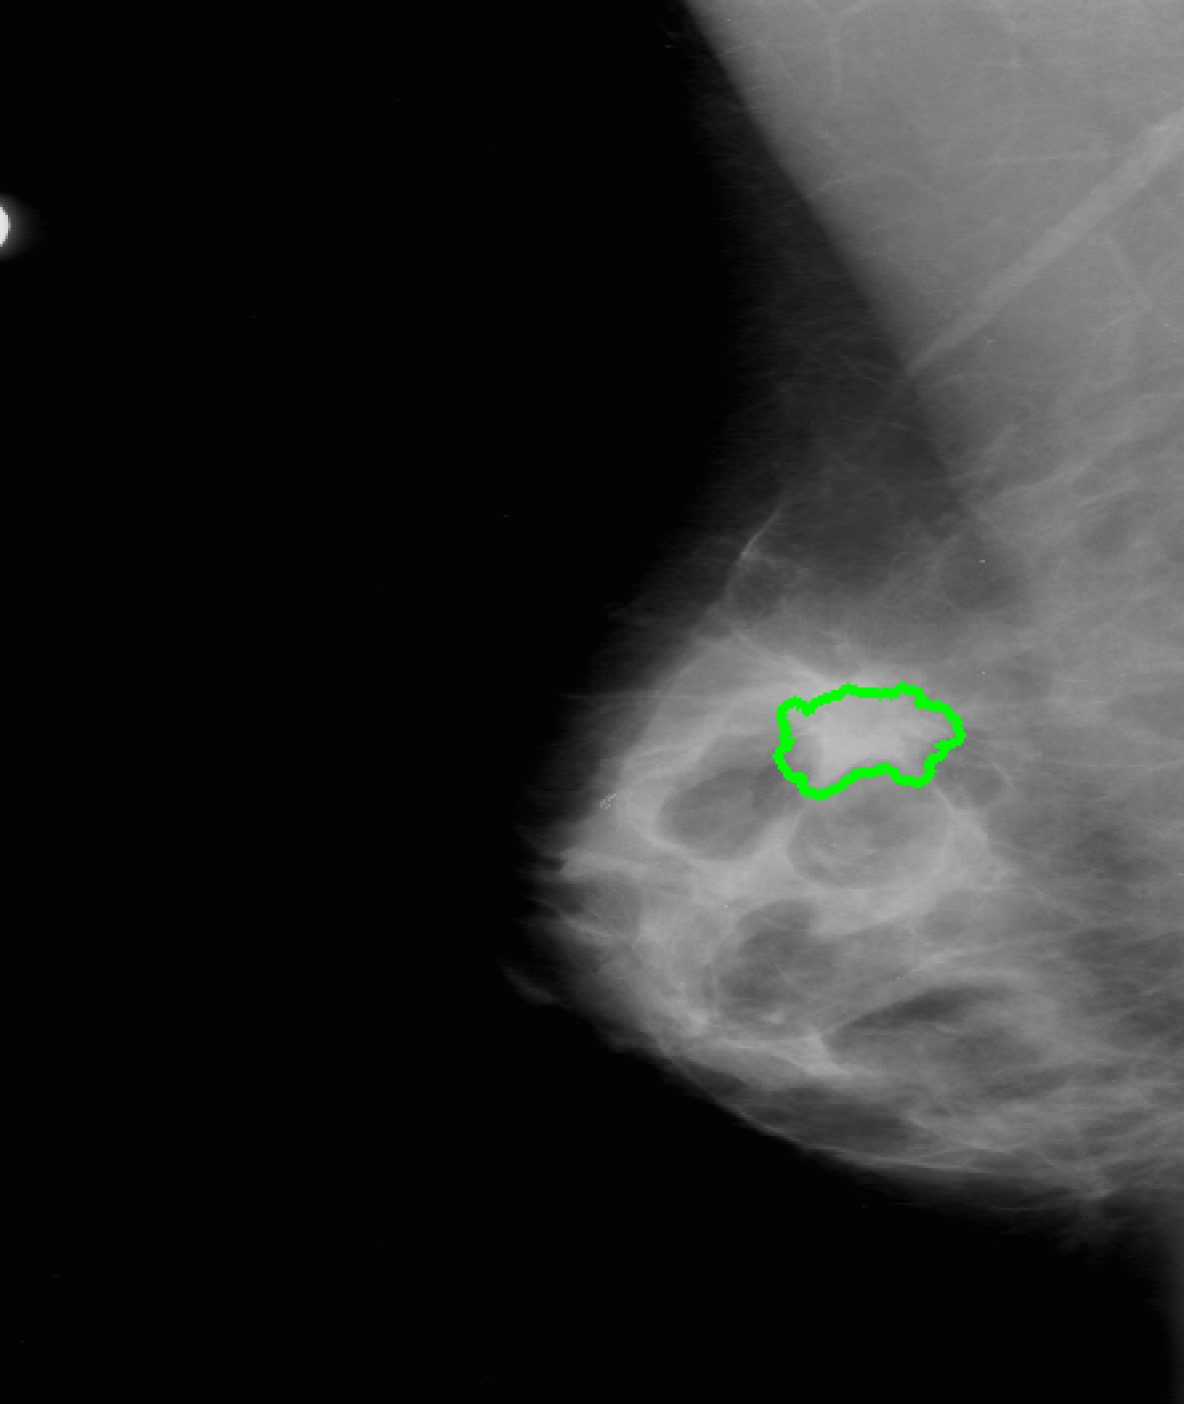

Figure 3: Result attribution heatmaps for mammography [17] and chest X-ray [14]: (a) original image overlayed with annotation contours (and arrows for missing GT), (b) our attribution framework. (c) GradCAM [25] (d) Saliency [26].

Attribution: We compared our attribution network against the gradient explanation saliency map [26] (SAL), and the network/gradient-derived GradCAM [25] visualizations. We limited our comparisons to these direct approaches, as they are widely used within medical imaging [13], and inherently valid [2]. Popular reference based approaches either utilize blurring, noise or some other heuristic [9, 8, 31], or were not available [7], therefore could not be considered. Quantitatively, we relate (i) the result-maps M^^𝑀\hat{M} to both organ, and ground truth (GT) annotations, and (ii) to each other. Particularly for (i) we studied the Hausdorff distances H𝐻H between GT and M^^𝑀\hat{M} indicating location proximity. Lower values demonstrate better localization in respect to the pathology. Further, we performed a weak localization experiment [8, 9]: per image, we derived bounding boxes (BB) for each connected component of GT and M^^𝑀\hat{M} attributions. A GT BB counts as found, if any M^^𝑀\hat{M} BB has an IOU 0.125absent0.125\leq 0.125. We chose this threshold, as a proficient classifier presumably focuses on the masses’ boundaries and neighborhoods, thereby limiting possible BB-overlap. We report average localization L𝐿L. For (ii) we derived the area ratio A𝐴A between M^^𝑀\hat{M} and organ-mask (breast-area) or whole image (chest X-ray). Again, lower values indicate a smaller thereby clearer map. Due to missing GT we could only derive (ii) for TBC. All measurements were performed on binary masks, hence GradCAM and SAL had to be thresholded. We chose the 50,75,9050759050,75,90 percentiles, i.e. compared 50,25,1050251050,25,10 percent of the map-points. Where multiple pathologies, or mapping results occurred we used the median for a robust estimation per image. Statistically significant difference between all resulting findings was formalized using Wilcoxon signed-rank tests, for α<0.05𝛼0.05\alpha<0.05. Additionally we followed [2], and tested our network with randomised parametrization (labels have no effect in our case).

As seen in Table 1, our framework achieves significantly lower H𝐻H, than either GradCAM or SAL at all threshold levels. Moreover, we report significantly better weak localization (L𝐿L) which underlines the higher accuracy of our approach. Qualitatively our attribution-maps are tighter focused (c.f. Fig. 3(b)) and enclose the masses. The former is also expressed by the lower overlap values A𝐴A. All p-values where significantly below 1e-21e-21\text{e-}2, hardening our results. Randomization of the ANN’s weights yields pure noise maps, hence we pass [2]’s checks.